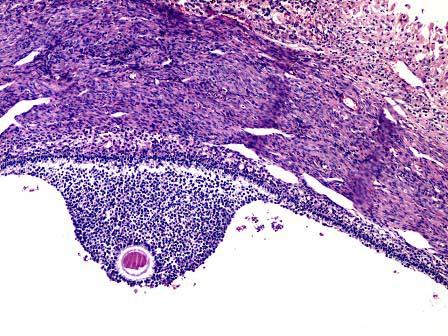

问题 女性,24岁因左腰部持续隐痛行检查,B超示左附件处囊状肿物。行左侧卵巢切除术。大体见卵巢切面多个囊腔,直径23.5cm,囊壁极薄,腔内面光滑,内含清亮液。镜下如图所见滤泡增大为囊状,粒细胞层增多达3层以上。应考虑为 ( )

选项 A.囊状滤泡 B.滤泡囊肿 C.黄体囊肿 D.卵泡膜囊肿 E.粒层黄素囊肿

答案 B